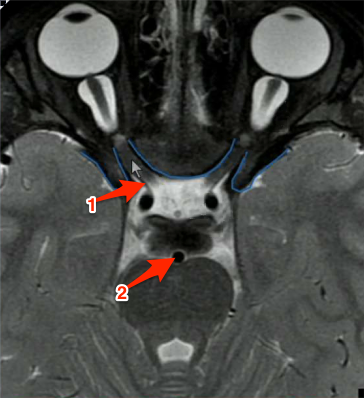

What structures are indicated below?

1) Opthalmic artery branching from carotid and going through the optic canal 2) Basilar artery

Where does the sympathetic innervation for the eye pass through?

Optic canal, it will be wound around the opthalmic artery.